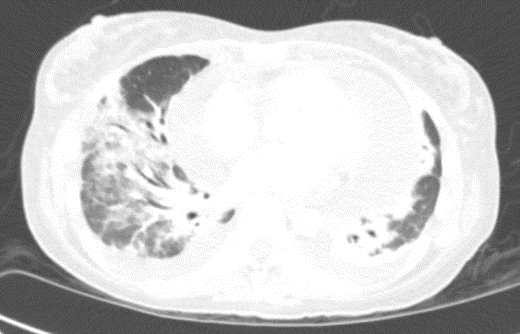

Laboratory studies showed pancytopenia, elevated inflammatory markers, and a high CMV DNA viral load. Echocardiography and chest computed tomography revealed a large pericardial effusion consistent with cardiac tamponade and bilateral patchy pulmonary infiltrates. Bronchoscopy, Bronchoalveolar Lavage (BAL), and transbronchial biopsy showed a lymphocytic-predominant inflammatory response, though histopathological evaluation was non-diagnostic.

Figure 2: CT chest showing lung infiltrates.